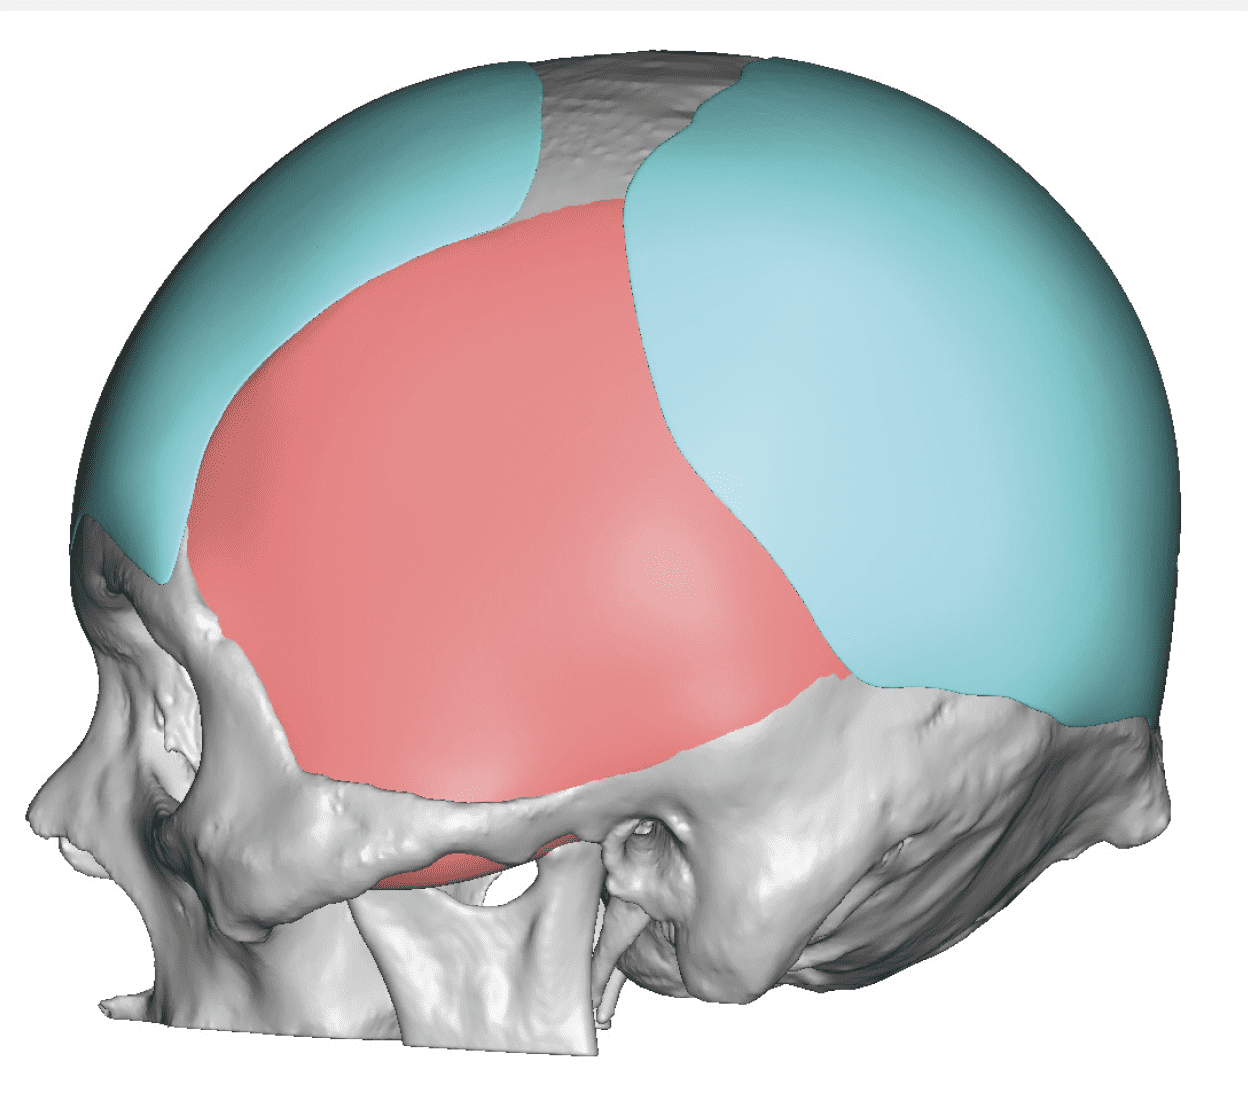

Patient 100

Desire for reshaping of an asymmetric flat back of the head in a shaved head male.

A combined back of the head reshaping procedure was done with a custom skull implant, sagittal ridge reduction and a right temporal muscle reduction.